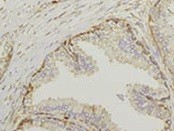

Detection of CNTFR alpha in Human Skeletal Muscle. CNTFR alpha was detected in immersion fixed paraffin-embedded sections of Human Skeletal Muscle using Mouse Anti-Human CNTFR alpha Monoclonal Antibody (Catalog # MAB303) at 5 µg/mL for 1 hour at room temperature followed by incubation with the Anti-Mouse IgG VisUCyte™ HRP Polymer Antibody (Catalog # VC001). Before incubation with the primary antibody, tissue was subjected to heat-induced epitope retrieval using VisUCyte Antigen Retrieval Reagent-Basic (Catalog # VCTS021). Tissue was stained using DAB (brown) and counterstained with hematoxylin (blue). Specific staining was localized to sarcolemma and sarcoplasm of skeletal muscle cells. View our protocol for IHC Staining with VisUCyte HRP Polymer Detection Reagents.